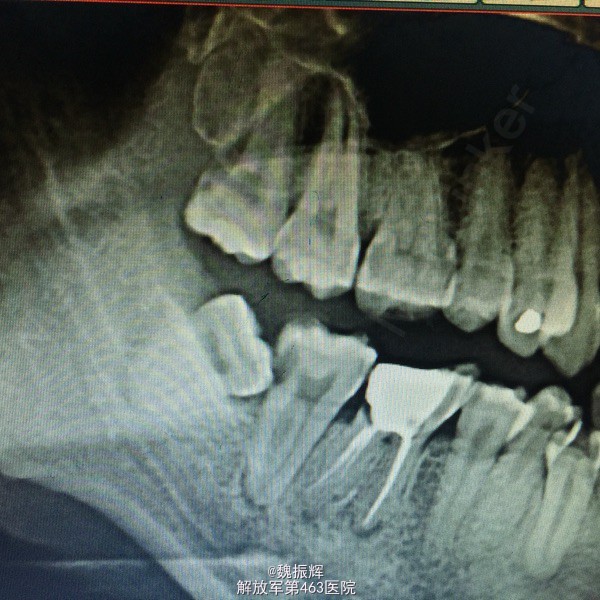

患者毕某,女性,右下后牙不适数日。数日来右下后牙自发痛影响睡眠,影响进食,来院就诊。

查体:47远中邻面龋坏,探(+),冷(+),叩(-),X线示远中龋坏近髓,48近中阻生,47,48之间食物嵌塞。

诊断:牙髓炎 处理:局麻下,47降牙合,去腐,开髓,揭髓顶冲洗,拔髓,根管疏通测量及机用镍钛器械进行根管预备,次氯酸钠进行根管冲洗,大椎度牙胶尖试尖,进行根管充填。Zoe暂封,观察嵌体修复。择期拔除48。

对于无咬合的阻生齿应该尽早拔除以免对其他牙齿造成损害。